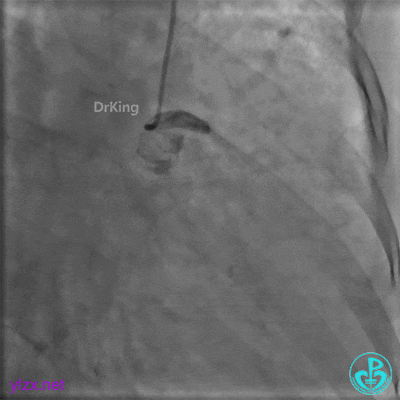

PL远端血管周围似乎有片状造影剂滞留。

经微导管PL分支造影,该如何解读这个经微导管造影结果?

经微导管造影。

远段造影剂外渗在增加,怎么办?